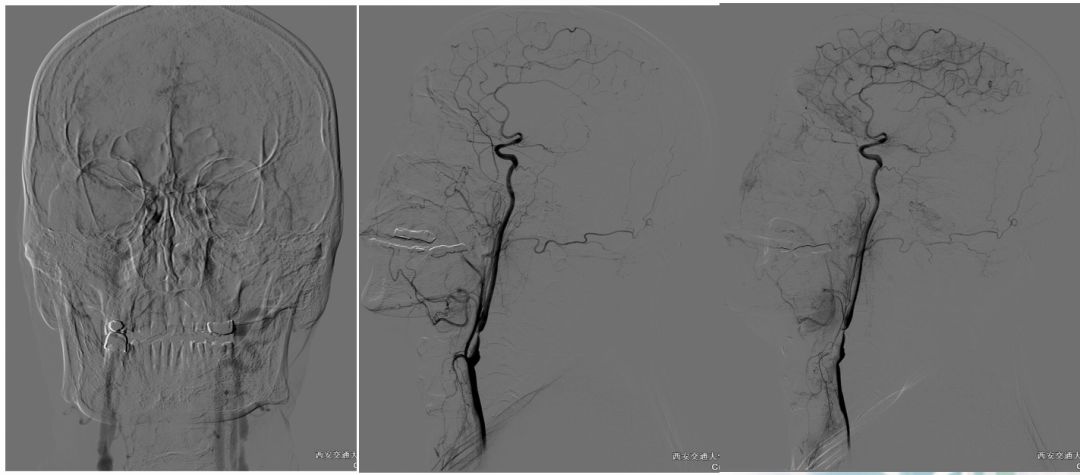

术前造影:

串联病变

ASITN/SIR 2级